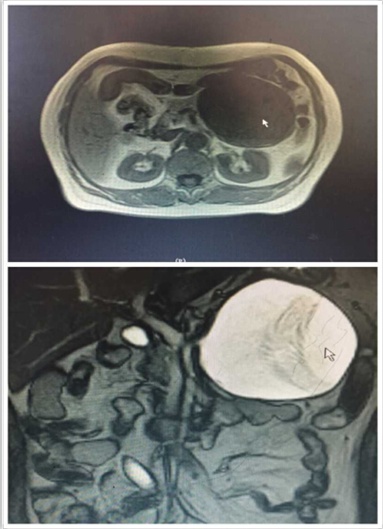

近日,我院肝膽外科入住一位65歲老年女性患者。該患者是一位退休工人,平日生活樸素,一年前自覺有上腹部隱痛不適,每次腹痛發(fā)作便自行于藥店買藥“治療”??墒墙螘r(shí)間,該患者感覺腹痛進(jìn)行性加重,腹部出現(xiàn)隆起,進(jìn)食少量食物便會出現(xiàn)腹脹、惡心、嘔吐不適,遂來我院就診。門診行腹部CT檢查發(fā)現(xiàn)胰腺巨大占位性病變(圖1),此時(shí)患者才恍然大悟,立即入住肝膽外科進(jìn)行治療。

圖1